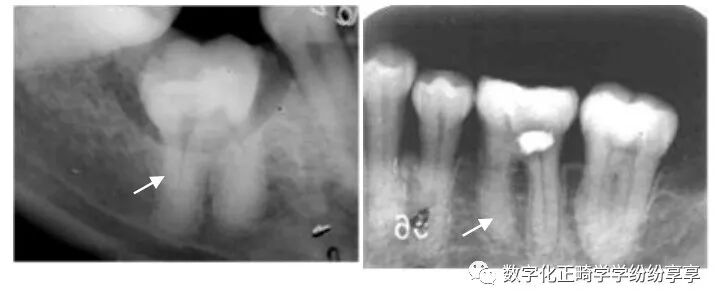

牙髓疾病 dental pulp disease:

牙内吸收

患牙髓腔扩大,呈圆形/卵圆形/不规则形密度减低透射影。发生于根管者有长短不一、粗细不均、沿根管的扩大影。髓室壁或根管壁变薄。可伴有根尖吸收/感染/折断。

牙髓钙化

阻射影;后牙为圆形、卵圆形,可游离于髓室内,也可附着于髓室壁;前牙为条状或针状,充满于髓室或根管内,周围有线状低密度影像环绕。

正常髓室及根管影像完全消失,不能辨别出髓腔界线,有的尚可见,但很细。